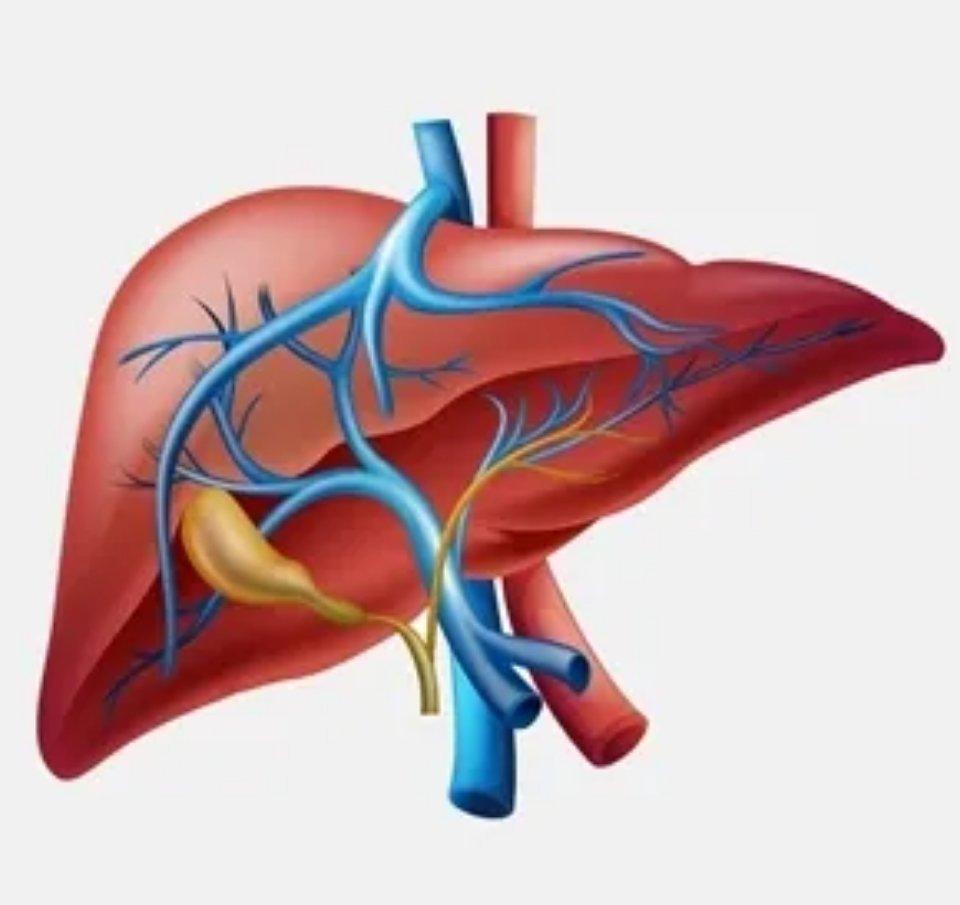

肝脏异常的4类指标,看完少走10年弯路! 1、谷丙转氨酶的升高。正常情况下,谷丙

2023-06-21 10:04